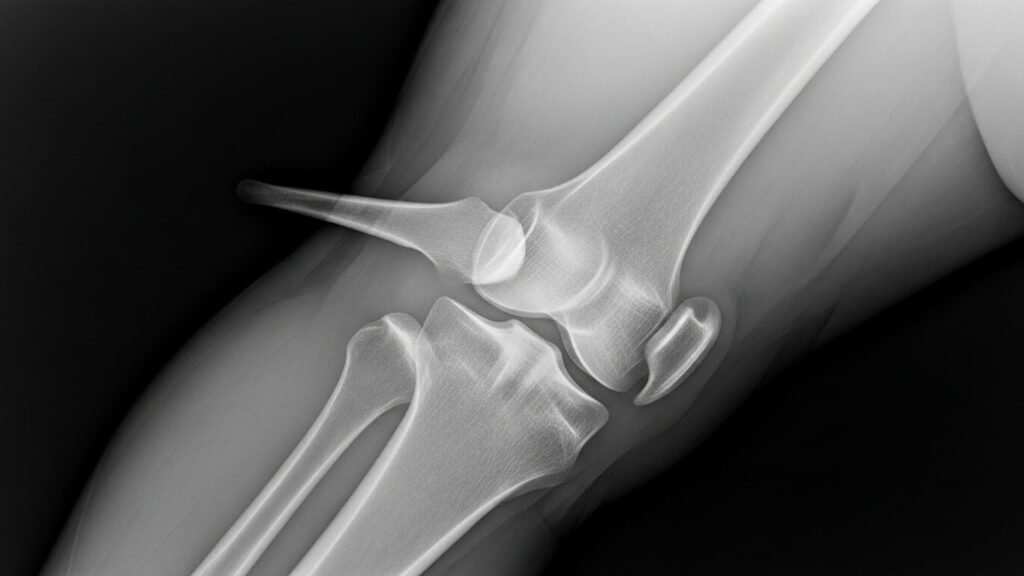

Knees and Long Bones

In growing kids, bony bumps called osteochondromas may develop near joints. They’re often harmless but can hurt if they press on muscles or nerves.

- X-rays – The most common way to see the size and shape of the bone growth.

In nearly all cases, exostosis shows up clearly on an X-ray, helping doctors decide what to do next. It’s important to diagnose exostosis early—especially in children—so treatment can begin if needed.